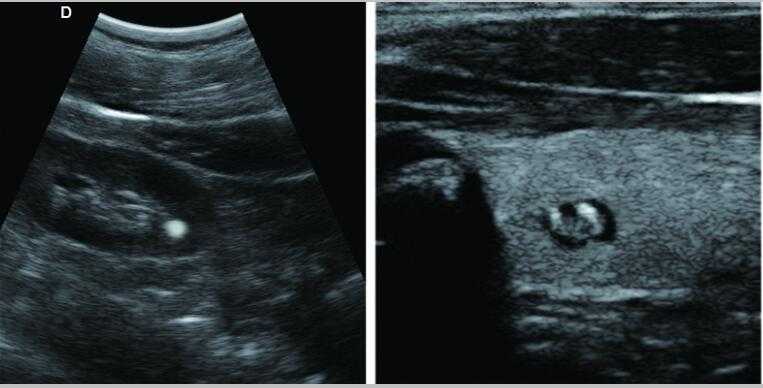

L3-VET筆記本式獸用B超機

牛羊馬豬犬貓及多種家禽、實驗動物、野生動物、及部分水生動物

L3-VET便攜筆記本式獸用B超機適用探頭